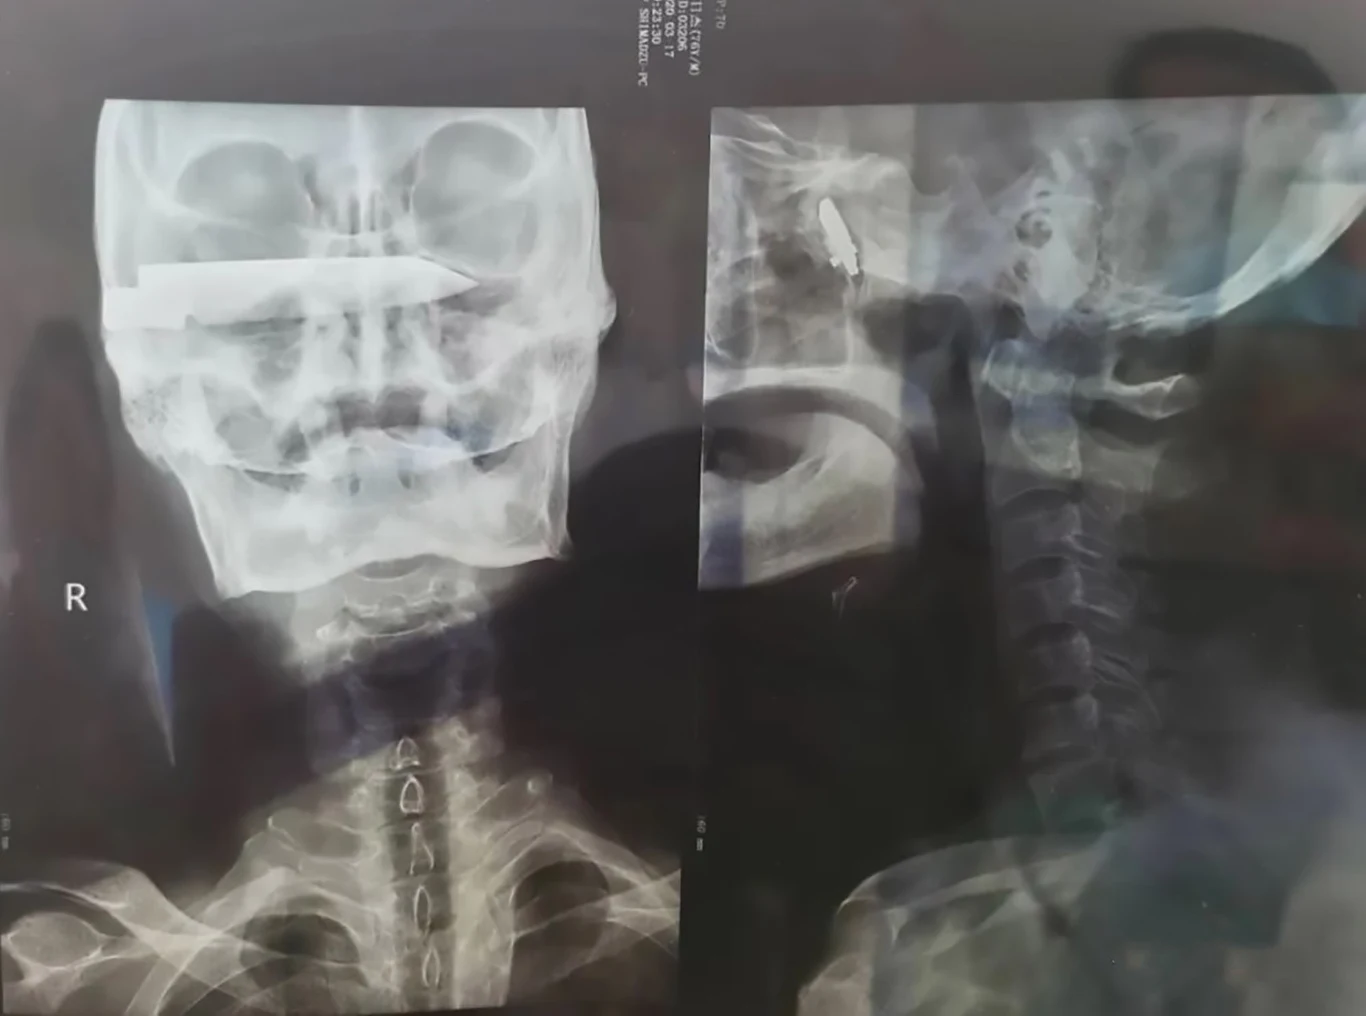

Cud. Tylko tak można opisać historię 76-latka o nazwisku Duorijie. W 1994 roku został on ofiarą brutalnej napaści, podczas której napastnik wbił mu 10-centymetrowe ostrze w głowę. Mieszkaniec Chin stracił wzrok w jednym oku i miał prawie pełny paraliż w lewej części ciała. Nie mógł się śmiać ani kaszleć. 26 lat później lekarze w końcu zakończyli jego koszmar.